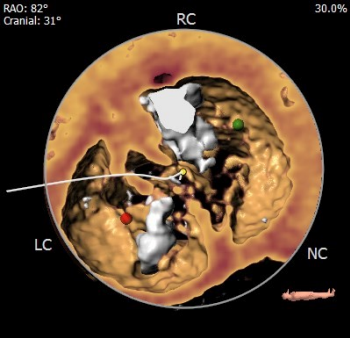

术前陈晓敏教授带领团队对这位患者进行了详细的分析,从CT分析结果显示,患者主动脉瓣为type 0型二叶瓣,瓣环直径为24.4mm,结合患者瓣叶钙化等情况,符合美敦力Evolut PRO 29mm瓣膜选型。经讨论决定以右侧股动脉为主入路,左侧股动脉为辅入路,术中进行23mm球囊预扩张,保证系统顺利跨瓣及释放,并采用世界先进的Cusp Overlap技术植入瓣膜 ,以更精准地释放瓣膜深,减少对患者传导系统的影响。

经左股动脉穿刺,置入6F股动脉穿刺鞘,将猪尾导管引导至主动脉根部,行主动脉造影。180bpm下置入23mm球囊扩张,沿导丝送入美敦力Evolut PRO经导管主动脉瓣膜系统,采用美敦力独有的commissual alignment技术,最大程度保护冠脉。递送系统顺利送入动脉系统并顺利过弓跨瓣,在采用世界先进的Cusp Overlap技术植入技术,最终目标位置完美释放,瓣膜立即工作,展开形态良好,无瓣周漏,无冠脉阻挡,无传导阻滞发生,术后无压差,血液动力学稳定,手术圆满成功。